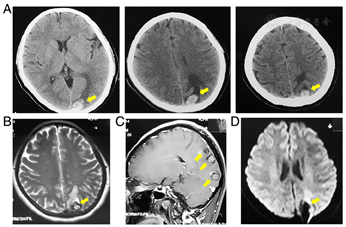

A-49-year-old female patient was admitted to local emergency department in November 2012 and August 2013, suffered from acute headache and dizziness, without any neurologic deficit. No history of hypertension or familiar CAs was recorded. In both time, Emergency head Computer Tomography (CT) has showed three hemorrhagic intracranial lesions in the left parietoccipital lobe (Fig. 1). Routine head MR scan also showed three small hemorrhagic lesions, with low signal on T1-weighted and high signal on T2-weighted images, without marked enhancement. A significant hypointese ring outside the lesion represents hemosiderosis, supporting diagnosis of CA. No acute infarction was detected in diffusion weighted imaging (DWI) (Fig. 1). Considering the good recovery afterwards and the risk of operation, she accepted the wait-and-see treatment.

In February 2014, she experienced recurrent symptoms. This time, she decided to accept intracranial lesions resection. She was admitted to our hospital in March 2014 for futher examination and surgical plan without any complaints of head or chest discomfort at that time.

In the next morning of hospitalization, she lost consciousness suddenly. Emergent CT indicated the third episode of hemorrhagic within the lesions. However, after regaining her consciousness, complete contralateral paralysis, facial palsy and aphasia -without prior seizure-, occured. Those symptoms could not be explained by the lesions.